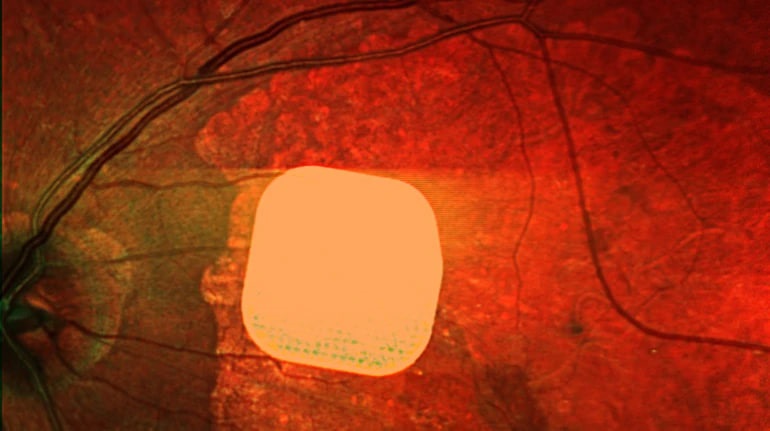

Британські лікарі успішно випробували новий електронний імплант Prima, який дозволяє частково відновити зір пацієнтам із макулодистрофією, що є головною причиною втрати зору після 50 років. Цей мікрочип розміром лише 2×2 міліметри встановлюється під сітківку ока, а пацієнт також отримує спеціальні окуляри з камерою і мінікомп’ютером. Камера зчитує зображення, яке потім передається на мікрочип, що активує клітини сітківки, після чого сигнал надходить до мозку. У дослідженні взяли участь 38 пацієнтів із важкими проблемами зі зором, і 84% змогли після імплантації розрізняти літери, цифри та слова. Лікарі вважають, що ця технологія може значно поліпшити якість життя людей зі зниженим зором, дозволяючи їм бачити краще і бути більш незалежними.